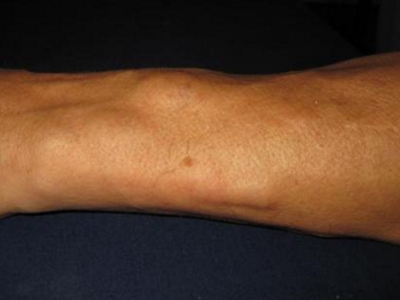

胳膊

软包

脂肪瘤胳膊上有一个大软包图

脂肪瘤出现在胳膊时,表现为局部皮肤大面积隆起,呈现为乒乓球大小的软包,按压时可适当移动,缓慢增大,对身体健康影响不大,但会影响外观,可手术切除。